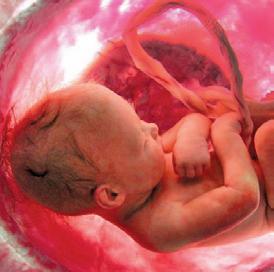

4th Month: 13–16 Weeks

By the end of the fourth month, the baby is 8–10 inches in length and weighs about one-half pound. Her ears are functioning and she hears her mother’s heartbeat, as well as external noises like music.12 Lifesaving surgery has been performed on babies at this age.